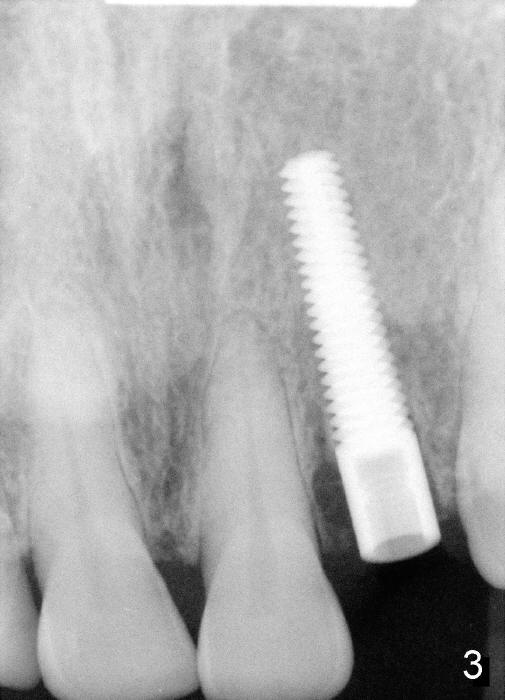

A 49-year-old lady has failed endo on the upper left lateral incisor (Fig.1,2). A gutta percha inserted to the buccal fistula (Fig.1 >) shows a mesial defect (Fig.2<). There is a large buccal apical defect, corresponding to the lesion shown in Fig.2 *, when the affected tooth is extracted. After thorough debridement and Clindamycin soaking, osteotomy is initiated in the palatal wall of the socket. Demineralized freeze dry cancellous bone graft is placed in the buccal defect. A 4x20 mm gingiva-level tapered implant is placed with insertion torque 50 Ncm (Fig.3). A 3x5 mm 20 ° offset abutment is inserted and cemented (Fig.4,5). A retentive groove is prepared on the abutment and the underlying implant; chamfer margin placed on the implant (Fig.4,5). A provisional is fabricated and cemented temporarily (Fig.6,7). Excess cement is removed, followed by removal of gingival retraction cord. There is no contact in centric and non-centric occlusion.

In case of a large bony defect, an immediate implant should be engaged into the palatal wall of the socket of the upper anterior teeth. The implant should be as long as possible to achieve primary stability.